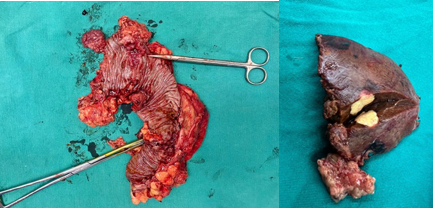

* Trường hợp số 2: bệnh nhân Triệu Xuân L, nam, 69 tuổi, được chẩn đoán ung thư đại tràng góc lách + đại tràng Sigma (u đại tràng 2 vị trí) di căn gan. Kết quả sinh thiết khối u đại tràng là ung thư biểu mô tuyến, không có đột biến gen KRAS hay BRAF cũng như không bộc lộ gen dMMR. Thông qua hội chẩn đa chuyên khoa, bệnh nhân được hóa trị tiền phẫu theo phác đồ hóa chất kết hợp điều trị đích CapeOX + Bevacizumab và đánh giá lại sau 2 chu kỳ. Kết quả cho thấy bệnh nhân đáp ứng tốt với điều trị, thể hiện trên cắt lớp vi tính và cộng hưởng từ, khối u giảm kích thước, tổn thương gan khu trú tại hạ phân thùy 6 kích thước 2x3 cm. Bệnh nhân đã được tiến hành phẫu thuật nội soi hoàn toàn cắt đại tràng trái (cắt đoạn đại tràng có 2 khối u và thực hiện miệng nối trong cơ thể giữa đại tràng ngang - đại tràng sigma, được thực hiện bởi kíp Phẫu thuật Ống tiêu hóa) kèm cắt gan hạ phân thùy 6 (được thực hiện bởi kíp Phẫu thuật Gan mật) (Hình 4,5). Việc phẫu thuật nội soi có thể áp dụng với cả 3 vị trí tổn thương (2 u nguyên phát tại đại tràng và u thứ phát tại gan) chỉ trong 1 lần mổ giúp tối ưu so với mổ mở với đường mổ có thể rất dài (từ mũi ức đến xương mu) (hình 6,7), giúp bệnh nhân giảm đau đớn, phục hồi nhanh sau mổ (có thể vận động, ăn uống trở lại ngay ngày hôm sau dù trải qua đại phẫu), đảm bảo tối đa tính thẩm mĩ, ít biến chứng liên quan đến phẫu thuật về sau (tắc ruột, thoát vị vết mổ...).

Hình 5. U đại tràng 2 vị trí và nhân di căn gan đã được phẫu thuật